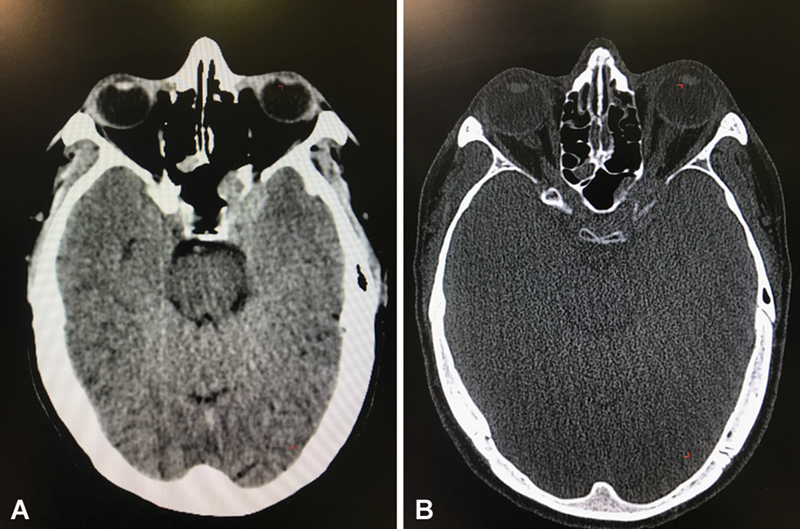

Anterior clinoid process metastases are rare. We present an unusual case of anterior clinoid process metastasis with sudden deterioration of visual function requiring emergency optic nerve decompression, resulting in recovery of visual function. The patient was a 41-year-old man with a diagnosis of leiomyosarcoma of the radius, operated on in 2014, with bone and lung metastases, who had been treated with chemotherapy and appeared to have stable disease at his last follow-up. Six years later, he developed a 1-month history of progressive unilateral loss of visual acuity and visual field defect (initially quadrantanopia that progressed to nasal hemianopia). Brain imaging showed a contrast-enhancing lesion affecting the left anterior clinoid process with extension to the cavernous sinus and sphenoid sinus, causing compression of the left optic nerve. Although the lesion could have suggested a meningioma given the location, in the context of the patient's oncological history, the diagnosis of metastasis was considered more likely. The patient was admitted to the hospital and, during the hospital stay, developed sudden left retro-orbital pain progressing to left amaurosis over approximately 8 hours. Urgent surgery was performed: a pterional craniotomy with partial tumor removal and optic nerve decompression with extradural anterior clinoidectomy. After surgery, the patient had an immediate but partial improvement in visual acuity and in the visual field defect. Metastasis to the anterior clinoid process is very uncommon, with only one case previously reported in the literature. In cases of visual impairment, symptoms may deteriorate rapidly to complete loss of vision, so urgent decompressive surgery of the optic pathway may be indicated to recover visual function, although recovery may be partial.